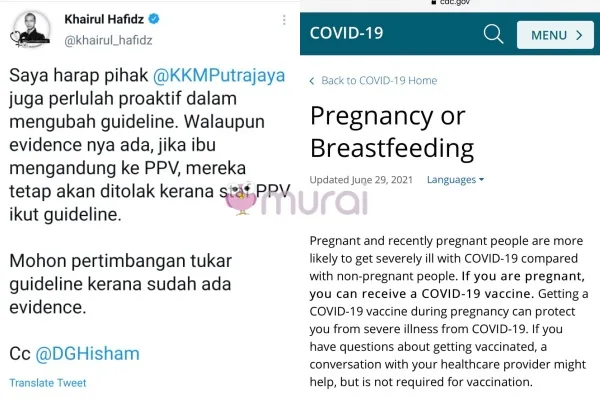

“Saya harap pihak @KKMPutrajaya juga perlulah proaktif dalam mengubah garis panduan. Walaupun buktinya ada, jika ibu mengandung ke PPV, mereka tetap akan ditolak kerana staf PPV ikut garis panduan.

Mohon pertimbangan tukar garis panduan kerana sudah ada bukti.” Ciap doktor Khairul